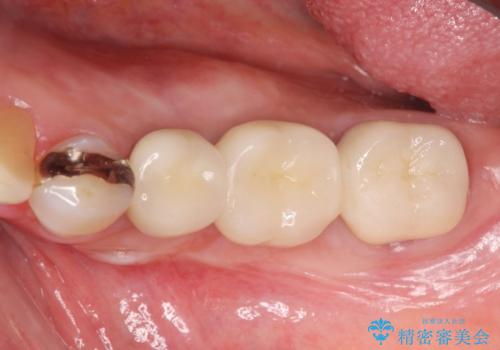

- 88万円(インプラント×2・アバットメント×2・クラウン×2・骨造成)費用は治療当時の料金となります

自家骨と人工骨による骨造成は、長期的に見て安定し吸収が少ないとされる骨の造成法です。

インプラント周囲に、必要十分な骨を作ることが長期渡りインプラントにトラブルを起こしにくい鍵となります。